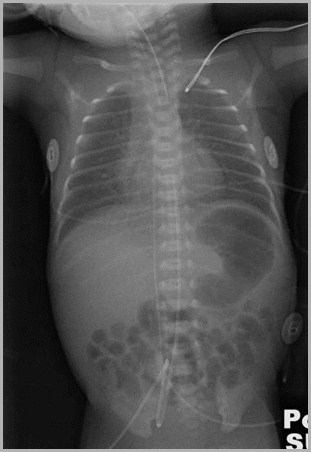

UAC and UVC Positions

Both should be above the diaphragm

UAC should be between T6 and T9

UVC should be in the IVC as it enters theright atrium (T8-T9)

Double lumen catheter is usually, but notalways, UVC

Umbilical venous catheter at junction between IVC and RAUmbilical artery catheter in distal aorta

Auckland